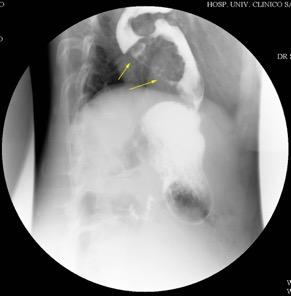

Líneas paraespinales formando un “paréntesis” por encima del diafragma. El signo señala el origen “intratorácico” de la lesión.

Conrad A et al. Pott’s disease associated with large and multiple abscesses in a 30-year-old migrant from Chad. BMJ Case Rep 2018

(lesiones toracoabdominales) La divergencia de las líneas paraespinales apunta a lesión toracoabdominal, que desde el tórax desciende y penetra en el abdomen.

Signo del “iceberg” positivo en Tb vertebral

Afectación por vía hematógena. Región dorsolumbar más frecuente. Afectación inicial: irregularidad de los platillos vertebrales, disminución del disco intervertebral con esclerosis ósea adyacente. Kim. Radiographics.2001